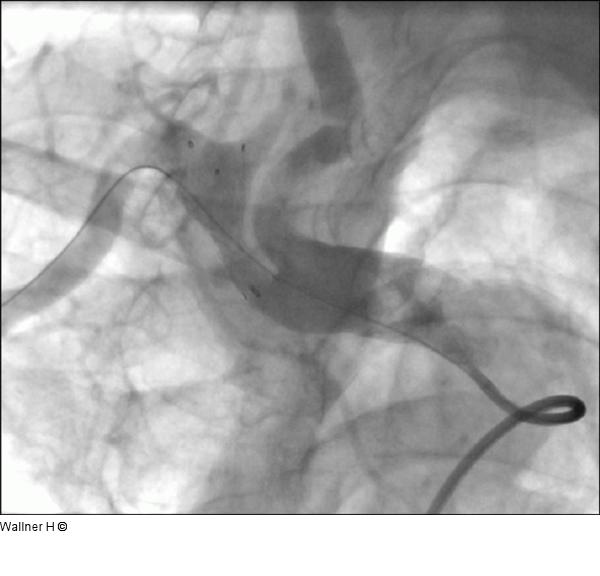

Abbildung 6: Abschlußangiographie Abschlußangiographie mit guter Stentplazierung bei uneingeschränkten Flußverhältnissen in der Arteria carotis communis und antegradem Fluß in der Arteria vertebralis. |

Abschlußangiographie mit guter Stentplazierung bei uneingeschränkten Flußverhältnissen in der Arteria carotis communis und antegradem Fluß in der Arteria vertebralis. |